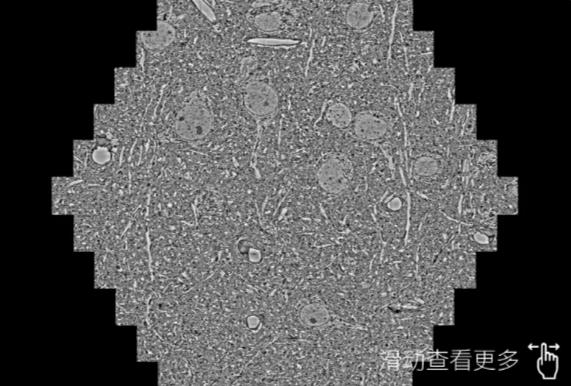

鼠脑切片。左图使用伊犁蔡司伊犁扫描电镜MultiSEM706对165μmx143pm面积区域成像,耗时仅需1.5秒。右图为鼠脑切片中30μm区域放大效果。样品由芝加哥大学B.Kasthuri提供。

使用蔡司高速伊犁扫描电镜MultiSEM对1mm²人脑皮层组织进行高分辨成像,并对其中的各种细胞结构进行三维重构分析。左图展示了2x3mm²组织平面中锥体神经元的三维重构效果。右图显示了局部体积神经元三维重构。图像由哈佛大学chtman实验室提供,渲染图由D. Berger 制作。